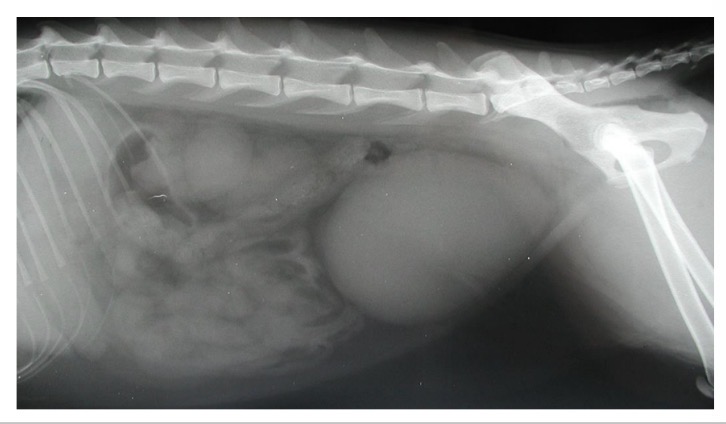

Hernia + body wall rupture → bladder displacement

Radiography - plain, positive contrast urethrography

What can positive contrast radiography detect in urethral obstruction

Displaced bladder, radiolucent calculi, soft tissue lesions

Radiography (Plain, retrograde urethrogram)